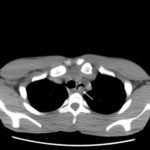

Significant findings:

After an unremarkable chest radiograph was obtained, a computed tomography (CT) scan of the chest was obtained due to possible co-ingestion of bones to rule out perforation. The CT scan demonstrated focal distention of the mid-esophagus due to an impacted food bolus (white arrow). An aberrant right subclavian artery (yellow arrow) was located just distal to the impaction site with partial compression of the esophagus (red arrow).